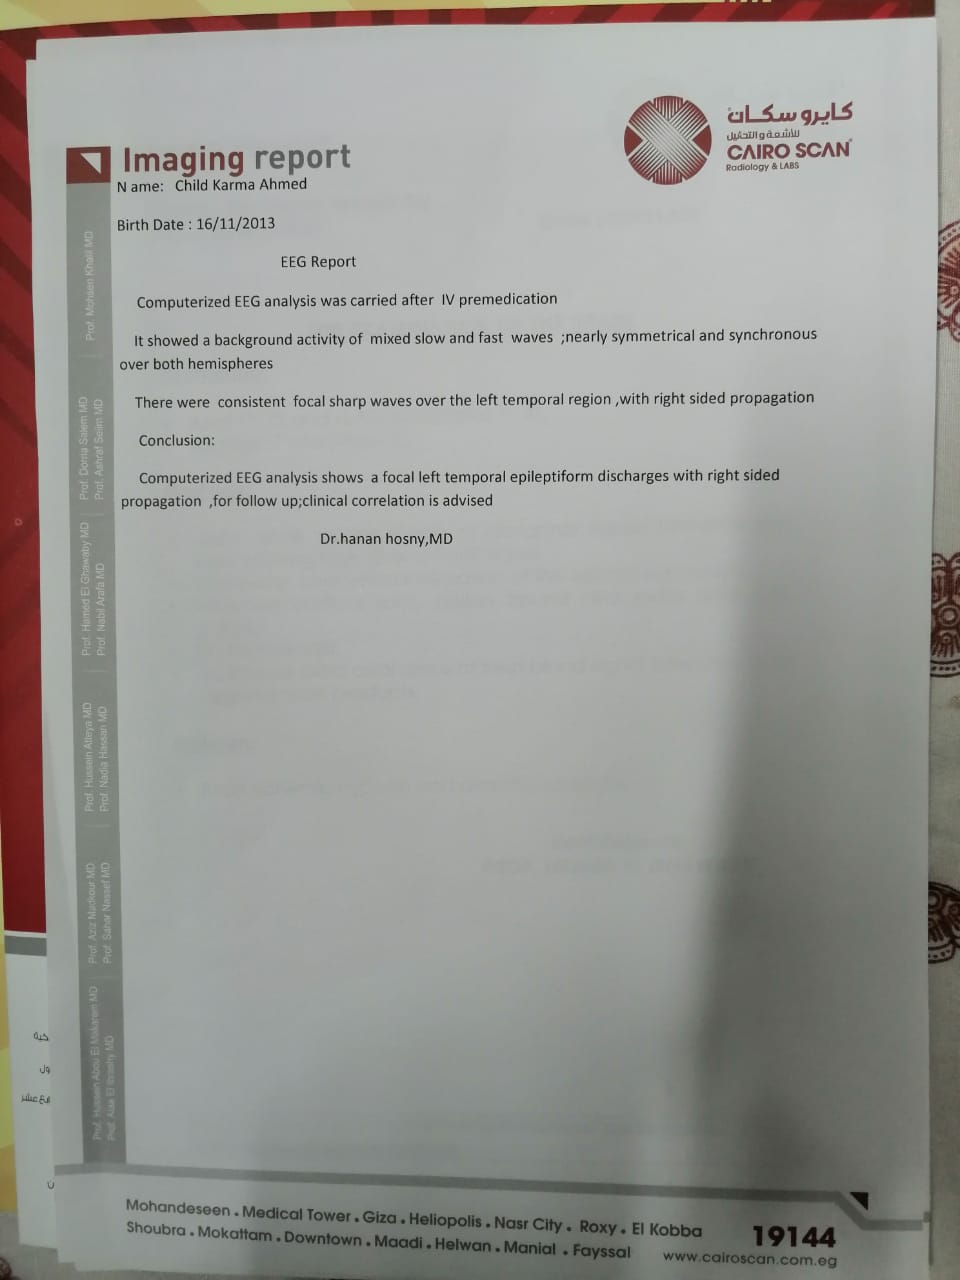

وأشار إلى أنه بعد خروج كارما من المستشفى تم إجراء فحوصات أخرى عليها، تبينت عدم التطابق بين التقارير الطبية لها بداخل المستشفى والفحوصات الجديدة.

وقال علي: "بنتي جالها ضمور في المخ وفي كل الحواس، بسبب الدوا الغلط، بنعملها علاج طبيعي بيتكلف في الشهر 20 ألف جنيه"، مشددًا": "هي بتفتح عينها بس".